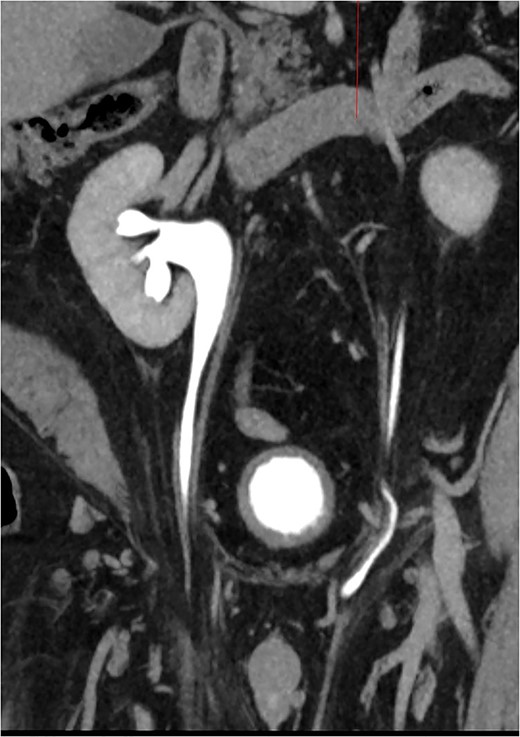

This is a 60-year-old male with a body mass index of 45.4 who was referred to the emergency room with a complaint of acute onset left flank pain. Past medical history was significant for hypertension and hyperlipidemia. Past surgical history was notable for appendectomy and multiple right lower extremity operations as a child to correct deformities from polio. He continued to require right lower extremity bracing. At the time of diagnosis, he had no additional gastrointestinal or urinary symptoms. Examination was notable for bilateral groin bulge suggestive of hernia versus hydrocele. The complete blood count, basic metabolic panel and urinalysis were unremarkable. A computerized tomography (CT) scan of the abdomen was performed and revealed bilateral inguinal hernias containing ureters and fatty tissue (Fig. 1). Mild right hydronephrosis was noted. Pain improved after the administration of ketorolac and patient was referred to general surgery for further evaluation.

CT Urogram with bilateral ureteroinguinal scrotal hernia. Maximum intensity projection image has been reformatted to highlight both ureters crossing the inguinal canals.